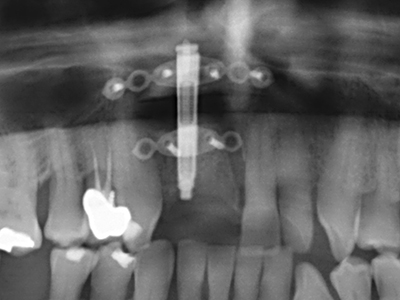

For removal of an implant, a vestibular bone cover that is replaced after removal of the implant screw can be prepared to retain the contour of the alveolar ridge.